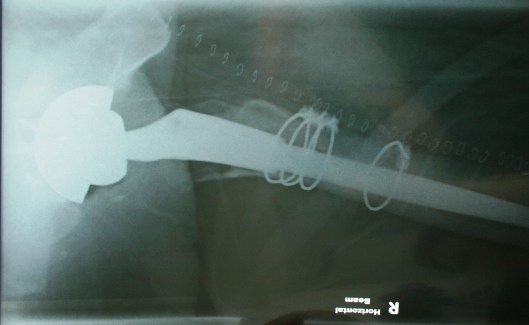

Here are the X-Rays of the revised hip – wired for everything except Digital FM, it seems!

- Split the femur to remove the previous Birmingham Spectron (S&N) femoral implant and remove excess glue and metallosis gunk.

- Bone graft to fill voids – wired femur back together to give bone strength while it heals – the fourth wire is to strengthen the mid femur because the new implant has a longer stem.

- New stem is press-fit.

- Then remove old acetabular cup – bone graft to fill out the void left – new cup put in and a couple of screws to make sure everything stays in place.

- Femoral head and cup are now inserted – ceramic on ceramic.

- The revision system is by Zimmer.

- To the right you can see the 38 or so stainless steel staples used to close the wound – removed on day 12 with only a few stings – no drama.

- The quality is not very good – taken on day one with me lying on a normal hospital bed and a very creative X-Ray team finding ways to get the required shots without moving me, the pain pump and the two drips too much – a real plumber’s muddle!

- Next week before I see the surgeon I will get a new set of X-Rays which should be a little crisper!